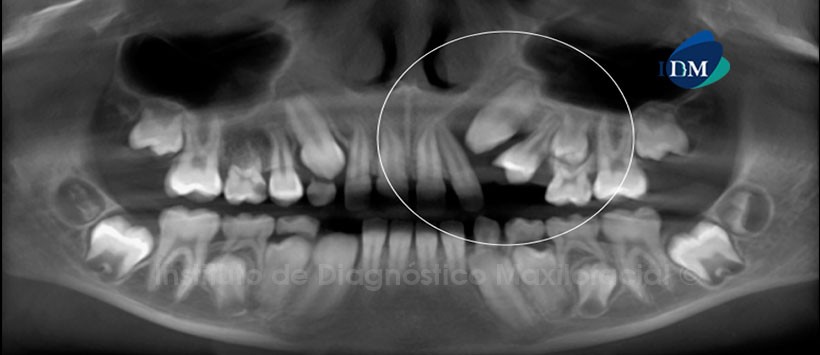

Paciente femenina de 10 años de edad que es referida al Centro Radiológico Óptimus, en la ciudad de Cartago – Costa Rica, por no evidenciarse clínicamente la pieza 24. La reformación panorámica nos muestra la presencia de una imagen isodensa de límites parcialmente definidos, localizada en la región canina del maxilar superior del lado izquierdo y que se encuentra aparentemente asociada a la pieza 23, la misma que ocasiona la divergencia radicular de las piezas 22 y 24. Por otro lado, se aprecia la agenesia de la pieza 15 (Fig. 1).

La tomografía computarizada de haz cónico mediante los cortes transaxiales y tangenciales nos muestra claramente que la lesión pericoronaria no sólo compromete la región de las pieza 23, sino que además se extiende hasta la región de las piezas 22 y 24. Así mismo, la lesión ocasiona el desplazamiento de las tablas óseas bucal y palatina. Signos imagenológicos sugestivos de una lesión benigna, descartar Quiste Dentígero vs. Tumor Odontogénico Adenomatoide (Fig. 2 y 3).